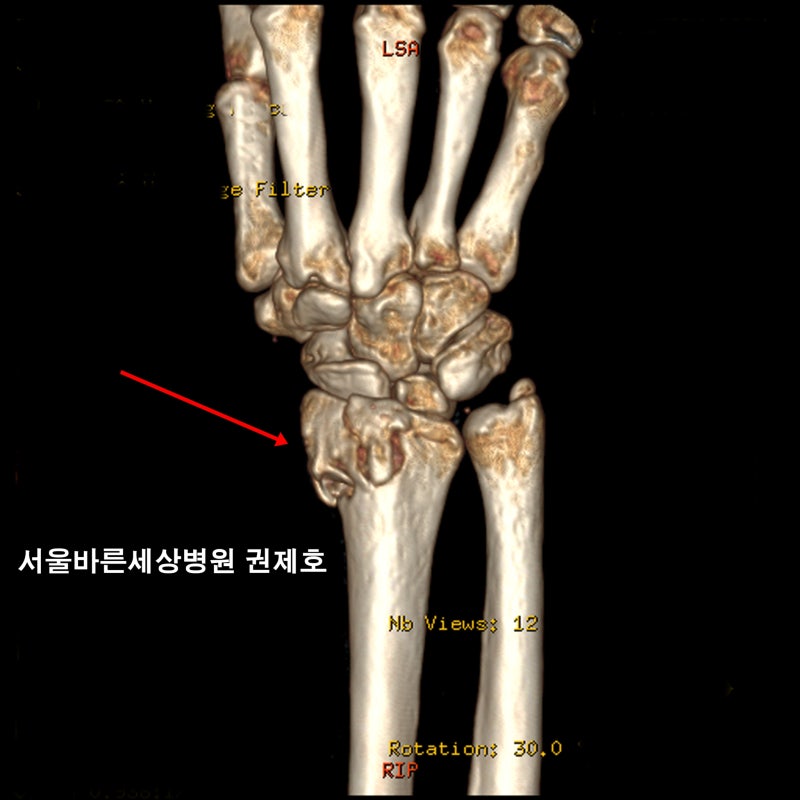

춥고 눈이 많이 오는 겨울철에 정형외과에서 가장 흔한 환자 중 하나는 손목 골절 환자입니다. 겨울에 발생하는 원위 요골의 경우 수술 빈도도 높은 편에 해당하여 수근골에서 주상골과 월상골에 접촉하여 수근골을 형성하게 됩니다. 관절면. 이 부분이 골절되어 관절면이 탈구되거나 틀어진 경우 수술적 치료를 통해 관절면을 복원하는 것이 매우 중요한데 해당 관절면이 정상적으로 회복되지 않는다면? 손목의 지속적인 통증이나 외상 후 관절염으로 인한 관절의 운동 범위 감소와 같이 삶의 질에 영향을 미치는 후유증이 지속될 수 있습니다. 먼저 손목 골절이 발생하면 X-ray와 CT를 통해 골절 여부를 확인하고, 탈구의 크기와 정도를 확인하여 심각하지 않은 경우 부목으로 비수술적 치료를 할 수 있다. 앞서 언급한 요골 관절면 손상에 대해서는 외과적 치료를 시행하는데, 외과적 치료 시 손상된 손목 아래쪽 피부를 4~5cm 정도 절개하여 골절 부위까지 도달하게 하고 주변 근육의 손상을 최소화합니다. 확인 후 양호한 상태를 유지할 수 있도록 환부를 얇은 금속판과 나사로 고정한다. 금속판과 나사가 견고하게 고정되어 있기 때문에 보존적 치료에 비해 비교적 치료기간이 빠릅니다. 손목 사용 가능. 수술 후 2~4주 정도 보조기를 착용하고 재활치료를 받아야 합니다.